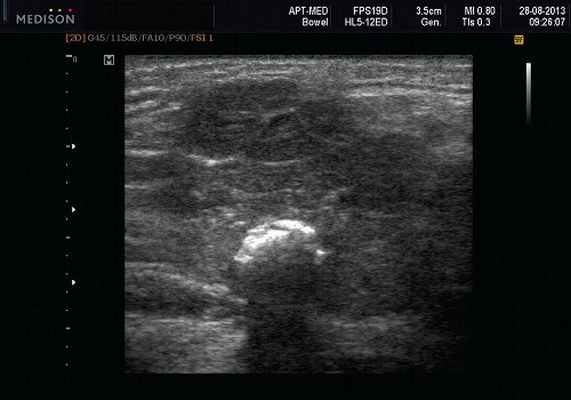

- обструктивные сиаладениты, развивающиеся при затруднении оттока слюны при обструкции выводного протока камнем (рис. 5-7) или сгустившимся секретом, а также вследствие рубцового стеноза протока. По распространенности процесса различают очаговый, диффузный сиаладениты и сиалодохит - воспаление выводного протока. Течение процесса может быть острым и хроническим;

Рис. 5. Камень протока поднижнечелюстной слюнной железы.

Рис. 6. Камень в паренхиме поднижнечелюстной слюнной железы.

Рис. 7. Камень в протоке поднижнечелюстной слюнной железы.